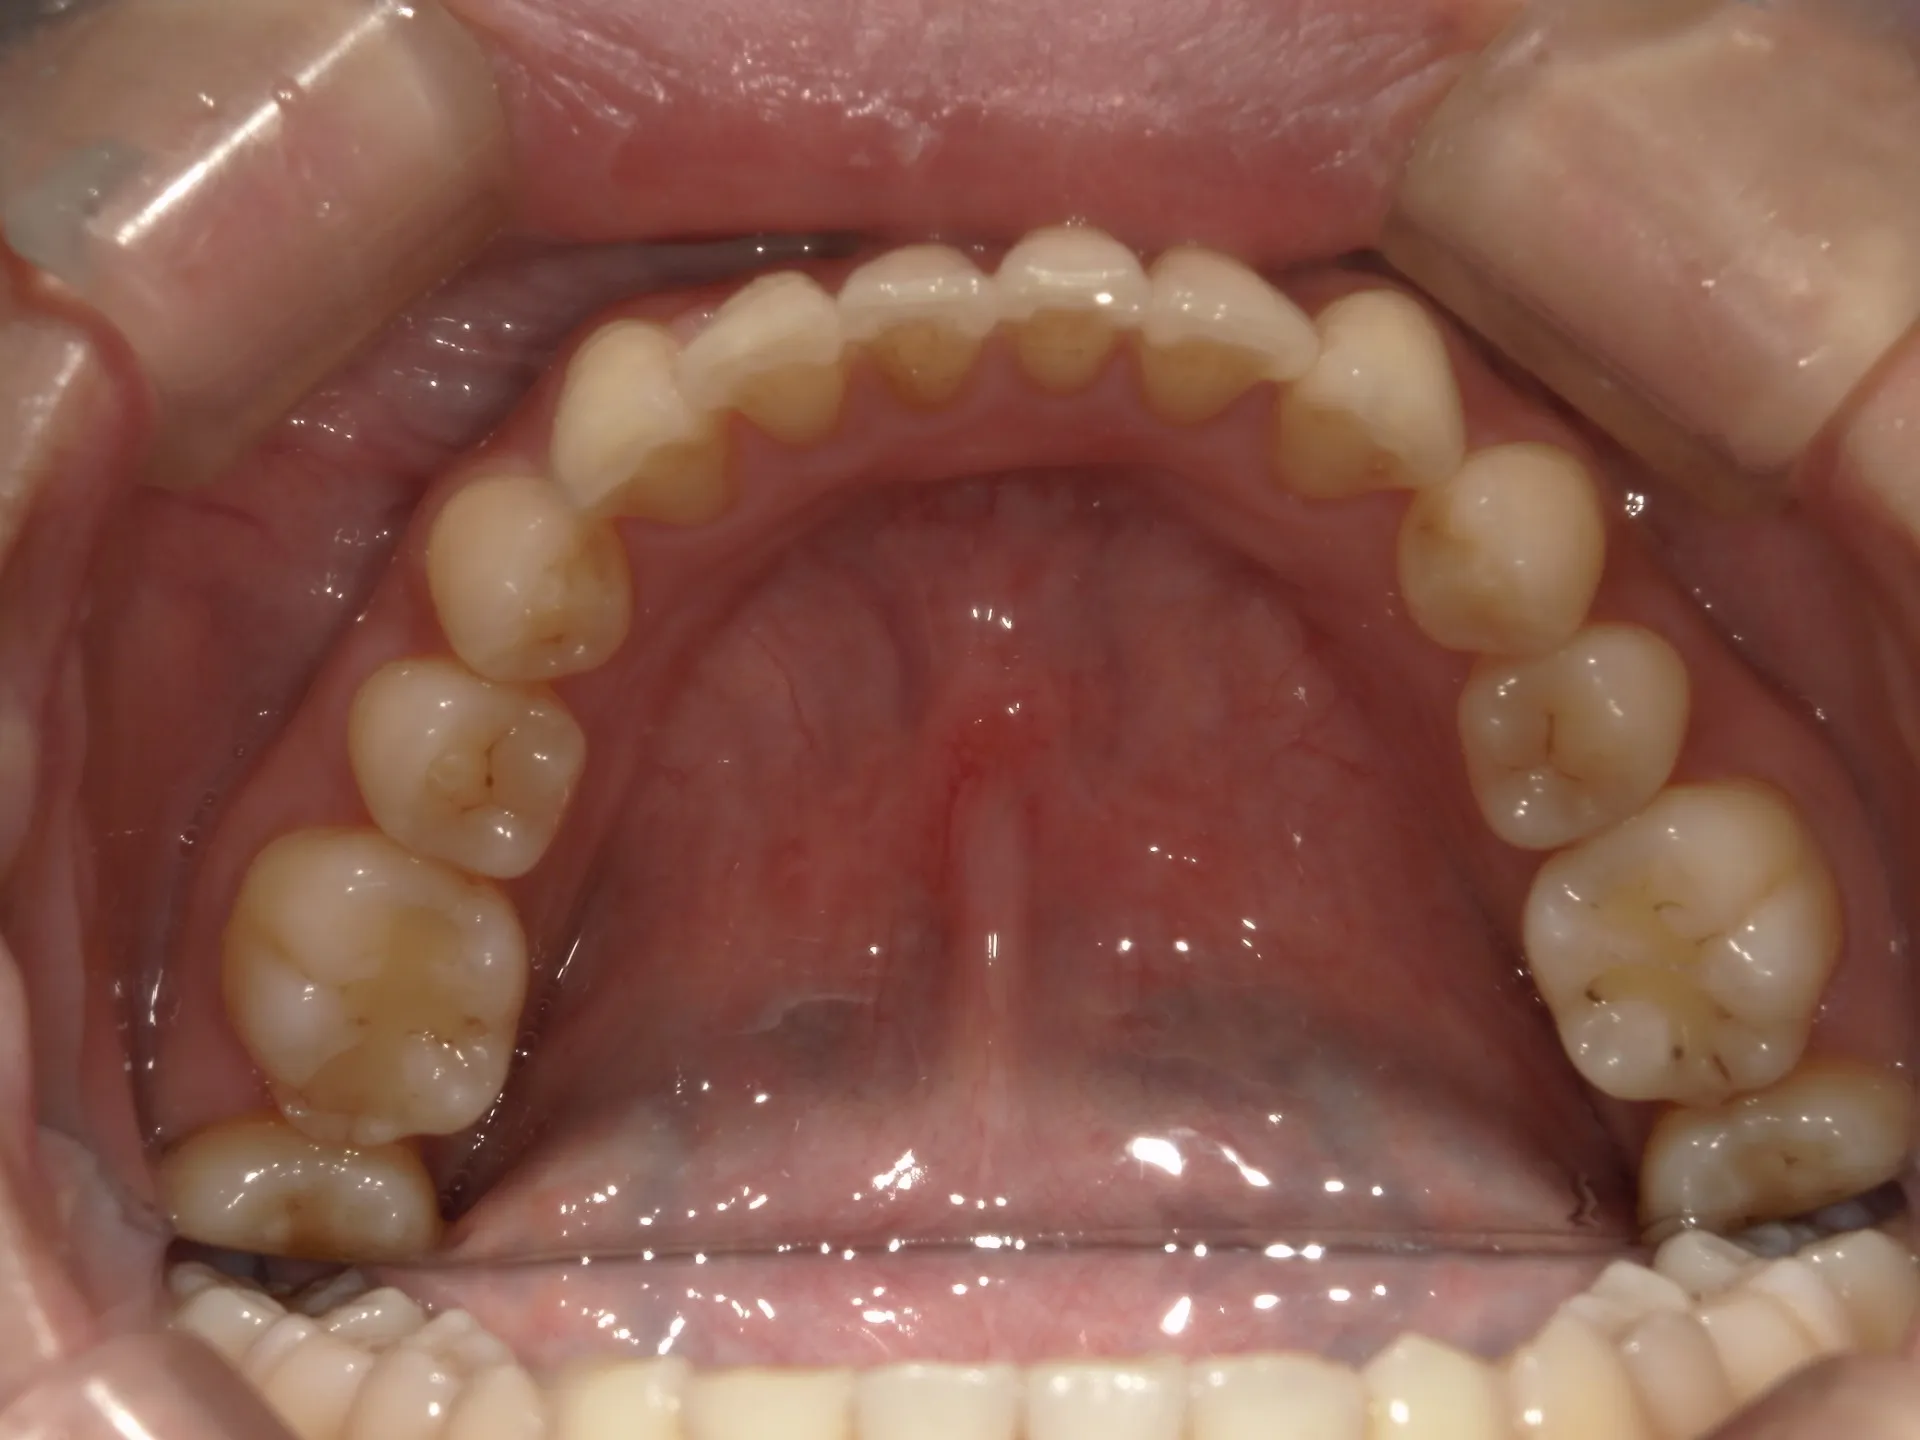

今回はねじれてしまった前歯の矯正治療をインビザラインというマウスピース矯正で治療した症例をご紹介いたします。